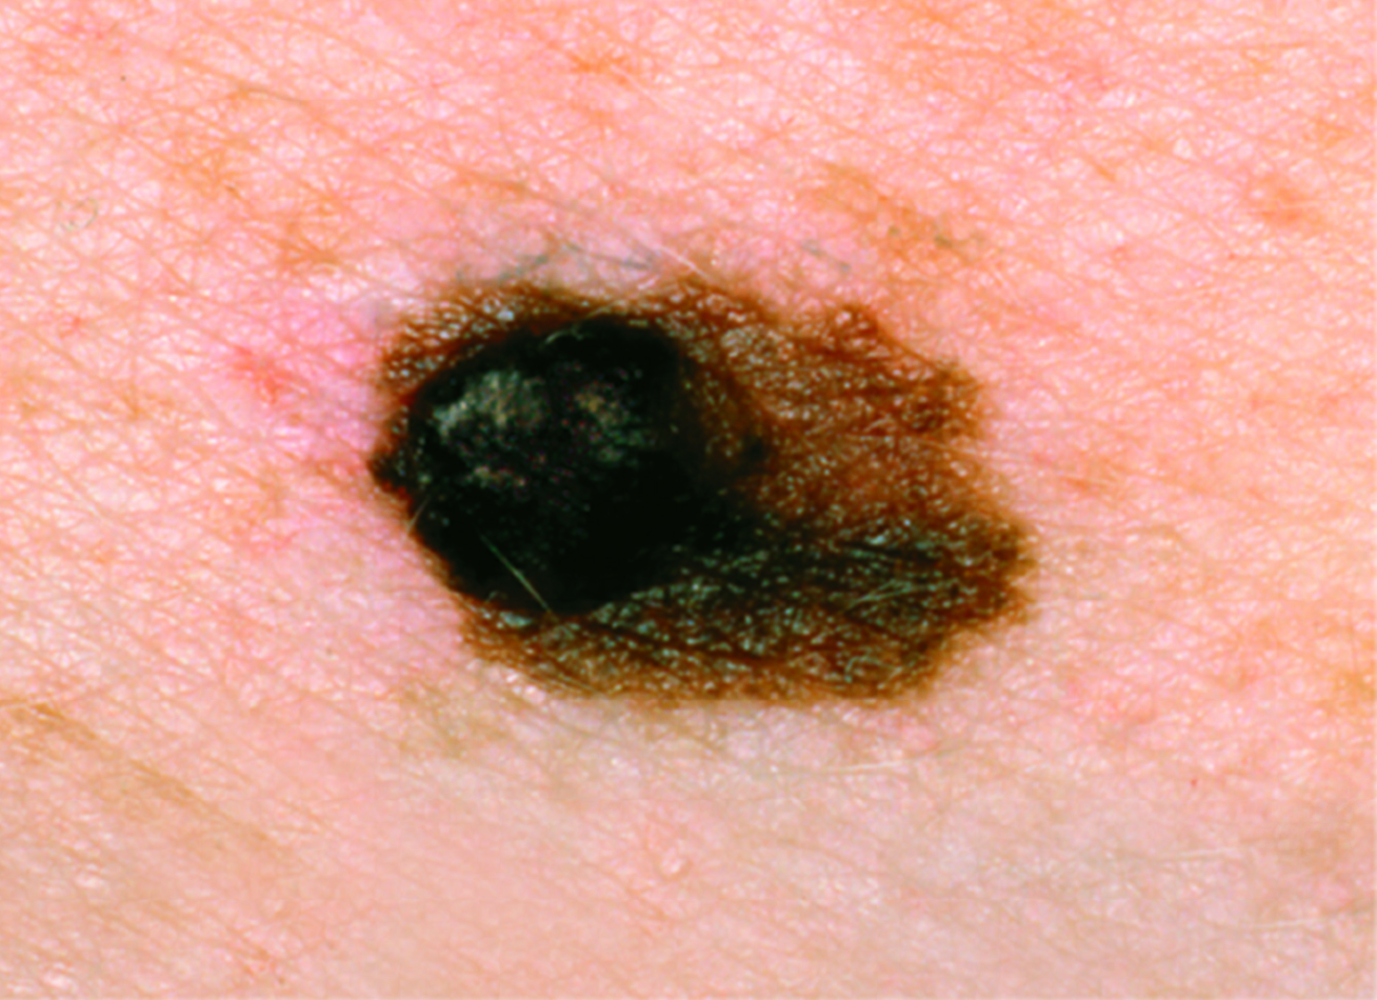

Melanoma Photos

Nodular melanoma on the leg of a Native American woman.

Photo: International Skin Imaging Collaboration

Amelanotic melanomas may be pinkish-looking, reddish, purple, normal skin color or essentially clear and colorless.

The power of denial can be strong. This man believed the large, dark growth on his back was a boil, despite oozing and bleeding for months. He kept bandaging it and thought it was just slow to heal. When he was finally referred to Dr. Sarnoff, a biopsy and other tests revealed a melanoma so large and deep that it had already spread to the man’s liver and brain. He was referred to an oncologist and began an immunotherapy regimen that did not appear to be working, which happens with some patients. (Thanks to recent innovations, there may be other treatment options, including participation in a clinical trial.) This is a powerful reminder of the importance of early detection.